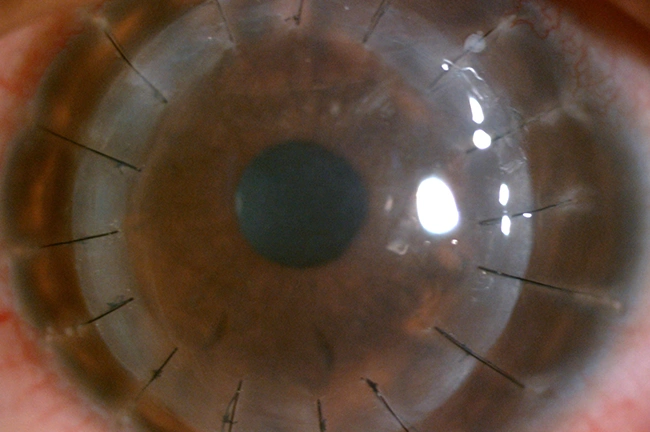

In cases where the progression of keratoconus is more advanced, surgical interventions may be necessary. Our skilled surgeons are proficient in performing advanced procedures such as corneal collagen cross-linking (CXL), Intra-corneal Ring Segments(INTACS), Corneal transplantation procedures like Deep Anterior Lamellar Keratoplasty (DALK) and Penetrating Keratoplasty (PK).